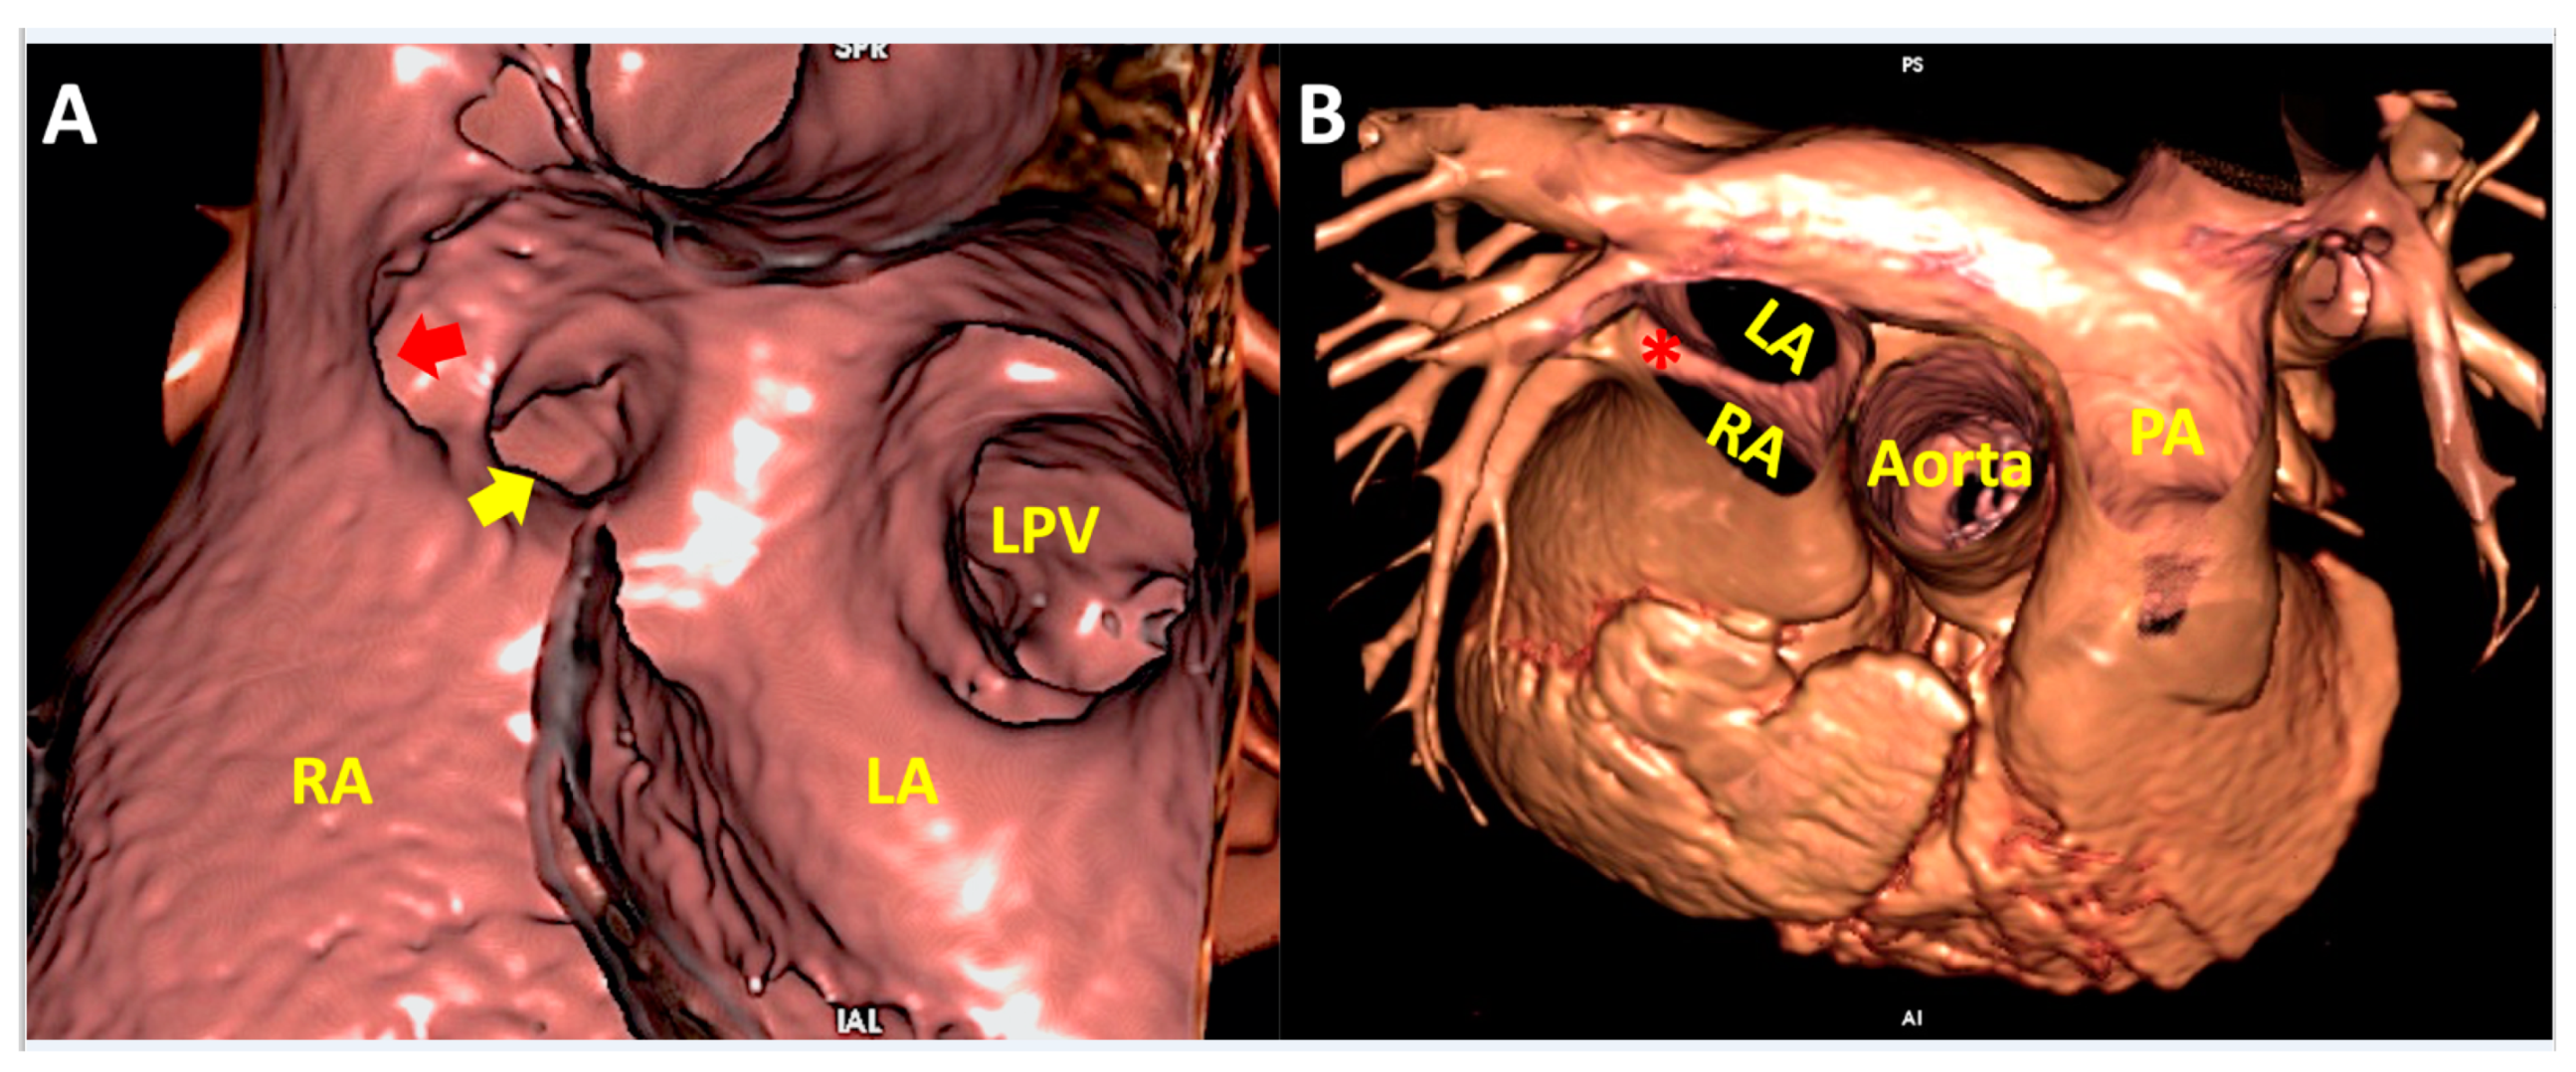

5. Clinical Implication in Acquired Heart Disease with Representative Cases

6. Clinical Implication in Congenital Heart Disease with Representative Cases